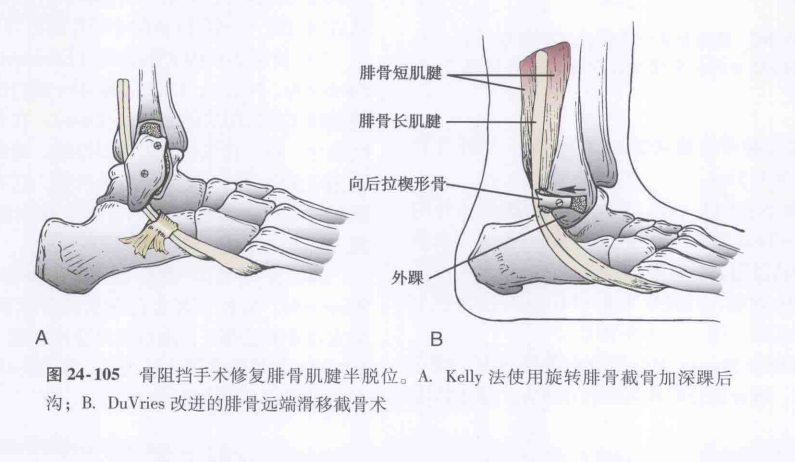

③外踝腓骨肌沟加深法;

图源:Coughlin M,Saltzman C,Anderson R,et al. 曼氏足踝外科学 [M]. 第 9 版. 唐康来, 徐林, 译. 北京: 人民卫生出版社,2015:1915.